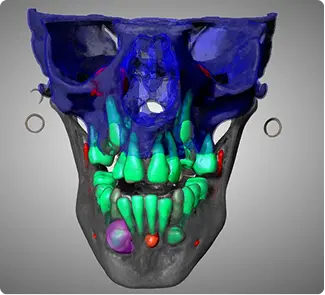

From routine 2D scans to complex 3D segmentations, get specialist-level interpretations tailored to your clinical needs.

High-precision DICOM conversion into 3D anatomical models and STL files ready for surgical guides.